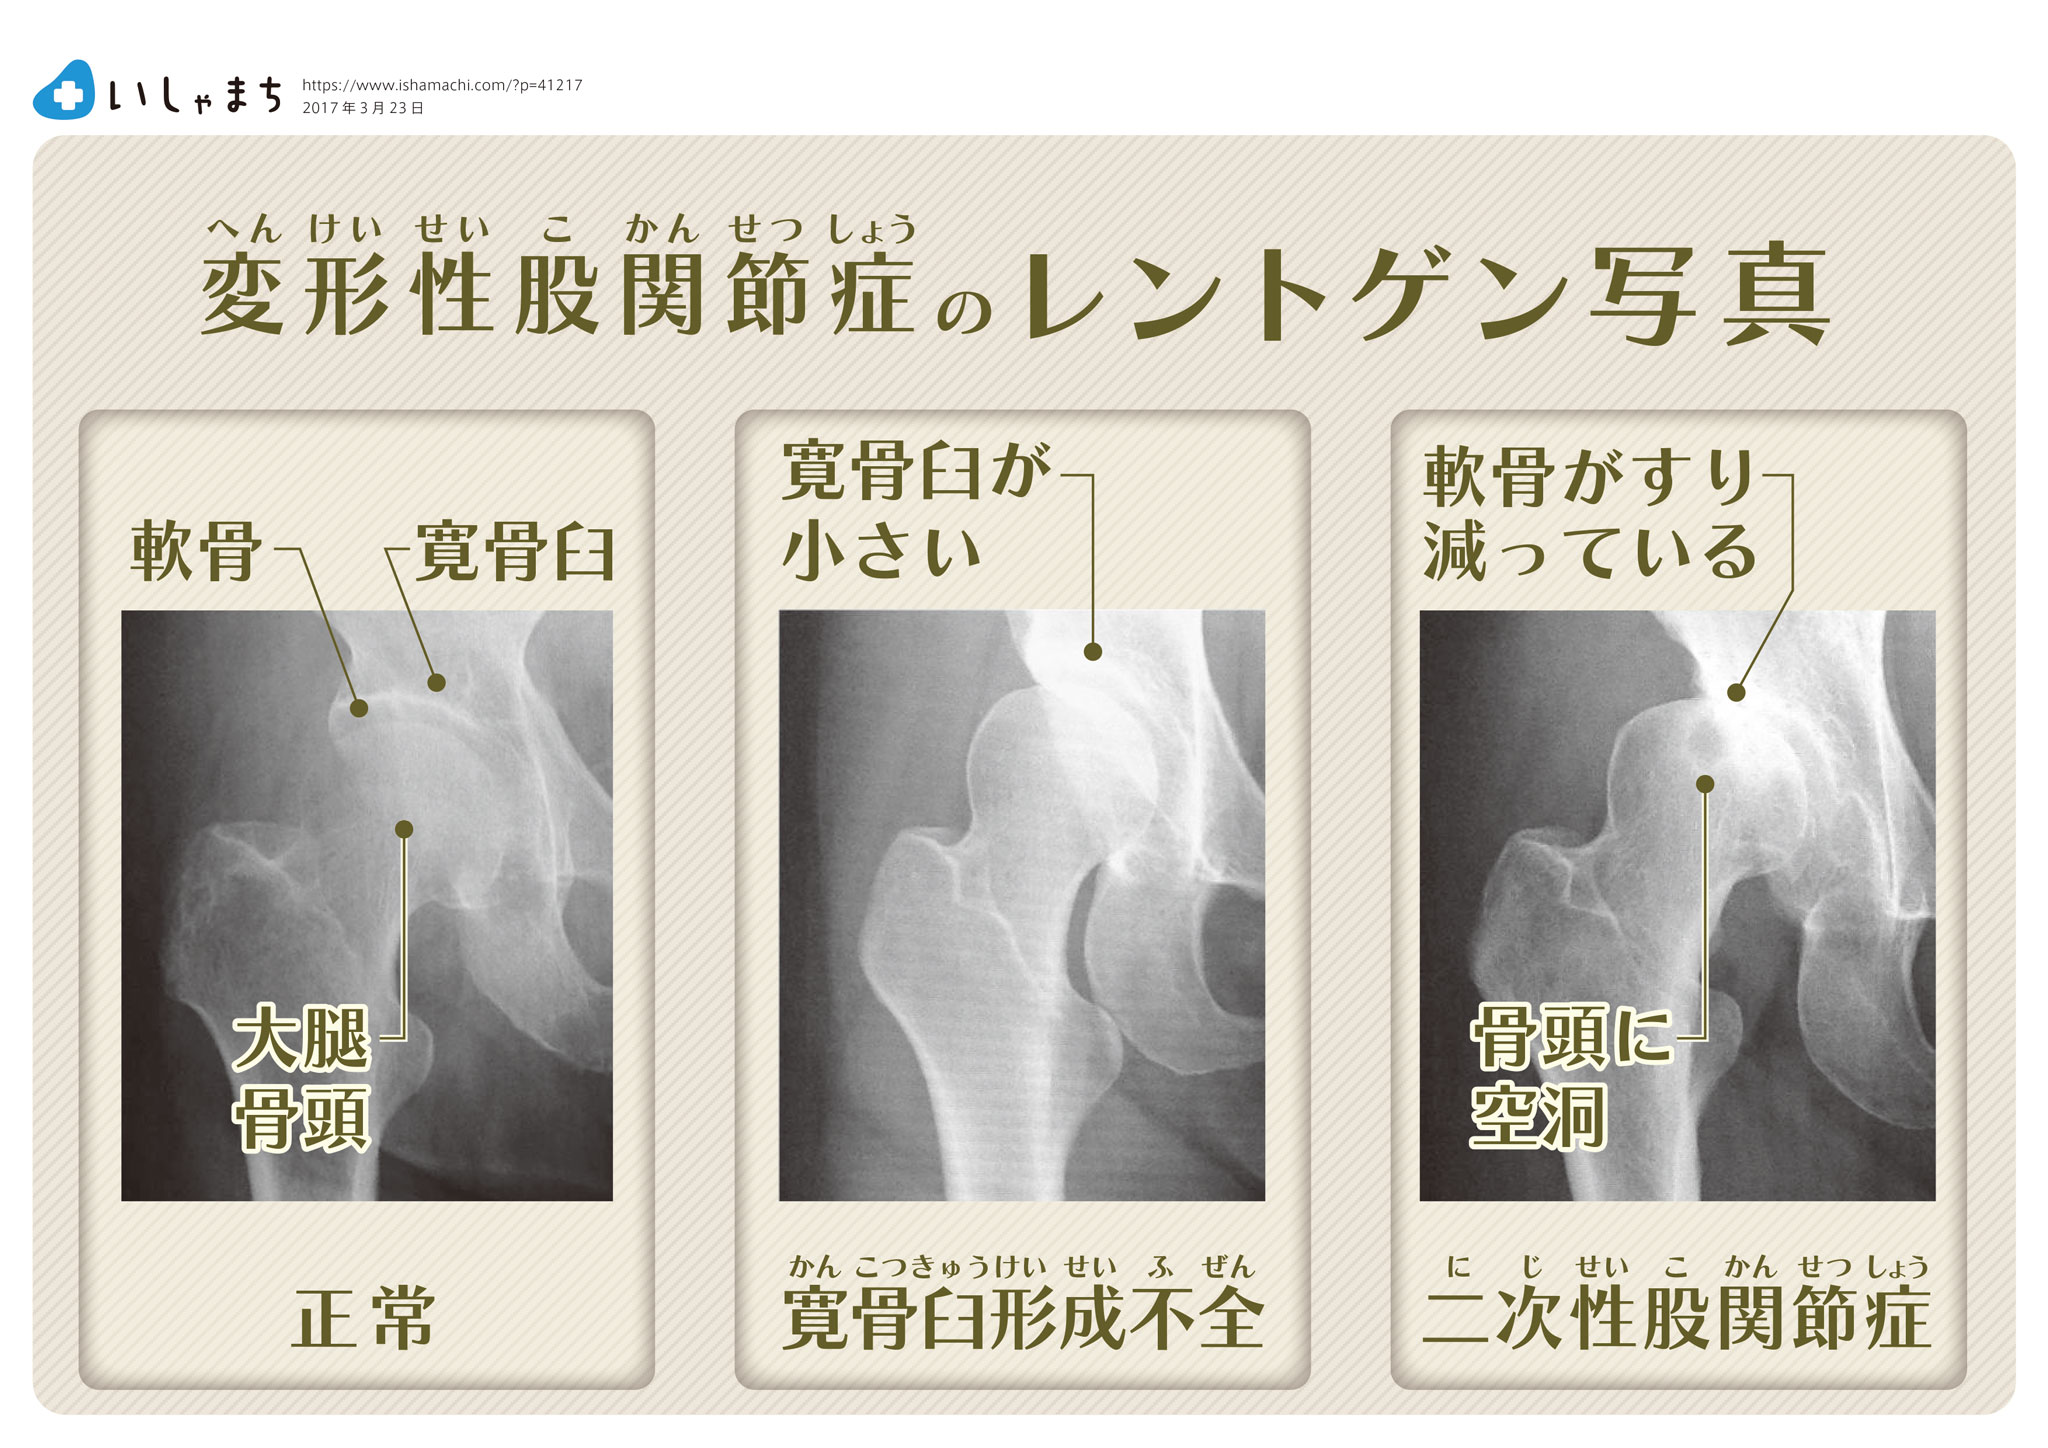

X線、血液検査、関節液分析などの追加検査を使用して、他の可能性を排除し、変形性関節症または他のタイプの関節炎の危険因子を判断する場合があります。

MRI では、X 線では必ずしも確認しにくい次のような変形性関節症の指標を特定できます。

変形性関節症と混同される可能性のあるものは何ですか?

変形性関節症は、関節の磨耗によって引き起こされます。関節リウマチ (RA)などの他の種類の関節炎は自己免疫疾患であり、炎症を引き起こします。追加条件としては、

ただし、このような MRI の画像化は、変性症状と炎症症状を区別するのに役立ちます。